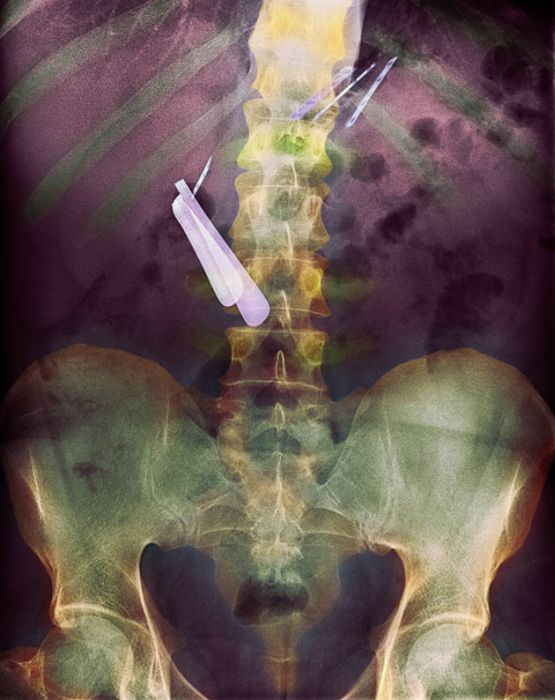

Рентгеновские снимки людей, которые умудрились сами или с чужой помощью разместить внутри своего организма разные посторонние предметы. От вилок и ножей до пуль и бензопилы (!!!). По этическим соображениям обычные снимки таких травм и повреждений выкладывать нельзя, зато рентгеновские можно – на них травмы видны достаточно условно, хоть и очень понятно.